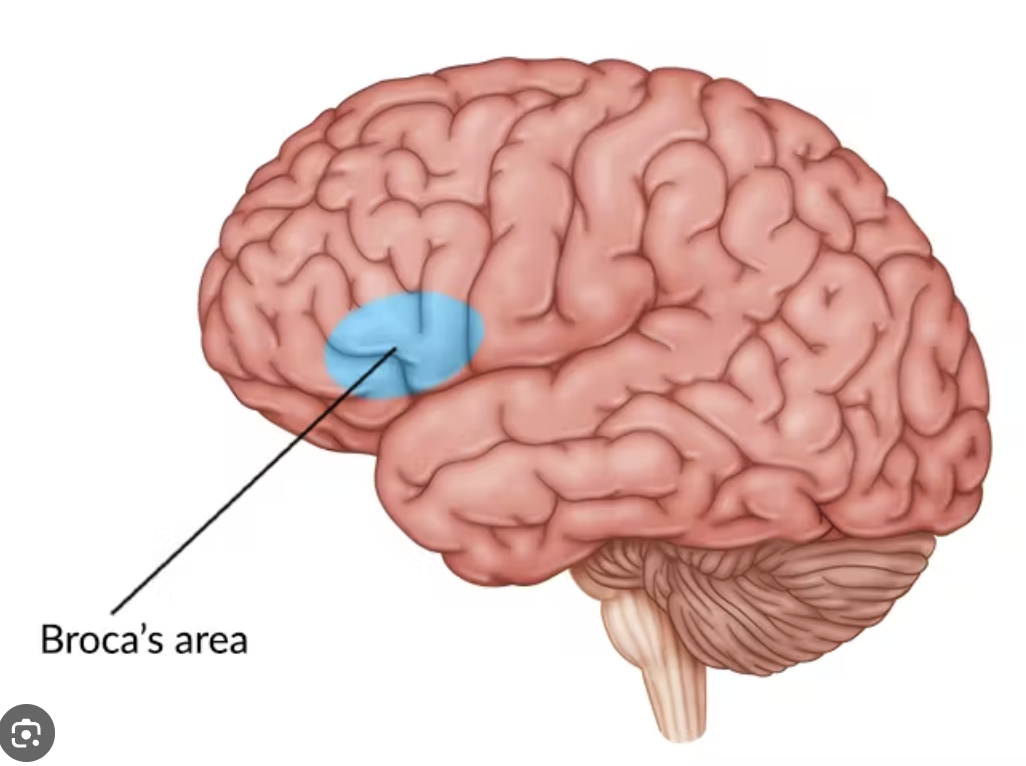

Which area is for speech production (expressive)

Broca’s area